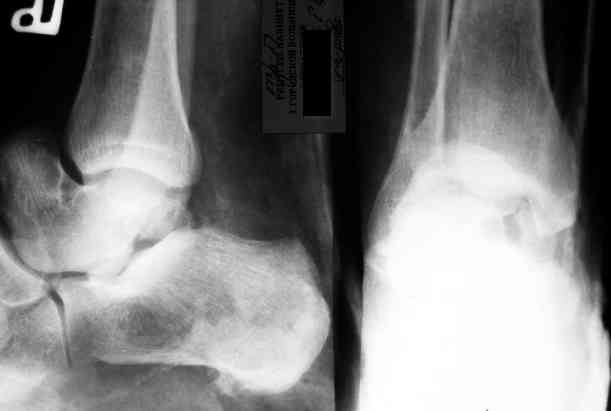

Уважаемый Александр! Как обещал представляю Р-граммы и операционные фото.

Мнение по поводу тарана? АН есть?

Типичная картина некроза.

На мой взгляд, у больного асептический некроз таранной кости, осложненный гнойным артритом голеностопного сустава (по снимку не понятно, что это - фистулография или простая рентгенограмма). Оптимален артродез голеностопного сустава, объем резекции таранной кости определится только интраоперационно. Большая проблема - метод фиксации. Работая, в основном, с пациентами пожилого и старческого возраста могу сказать, что ЧКОС они переносят плохо. Адекватный уход за аппаратом возможен только в условиях стационара. Возможность самостоятельной работы с аппаратом, например для ликвидации укорочения, крайне сомнительна. Кроме того, укорочение 3 см (до 5 см) у данной категории больных легче компенсировать ортопедической обувью. К сожалению и фиксирующие повязки (гипсовые и различные "касты")- не лучший вариант для пожилых людей (пролежни и флектены просто на "ровном месте"). В данном случае я бы применил простую "фиксирующею" компоновку аппарата Илизарова, с возможностью "отступления" к голеностопному брэйсу (тутору). Основная задача - максимальное восстановление самообслуживания больного и, по возможности, избежать "этапных" операций.